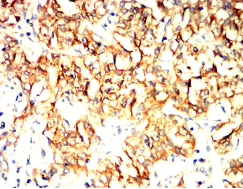

IHC    1/200 - 1/1000